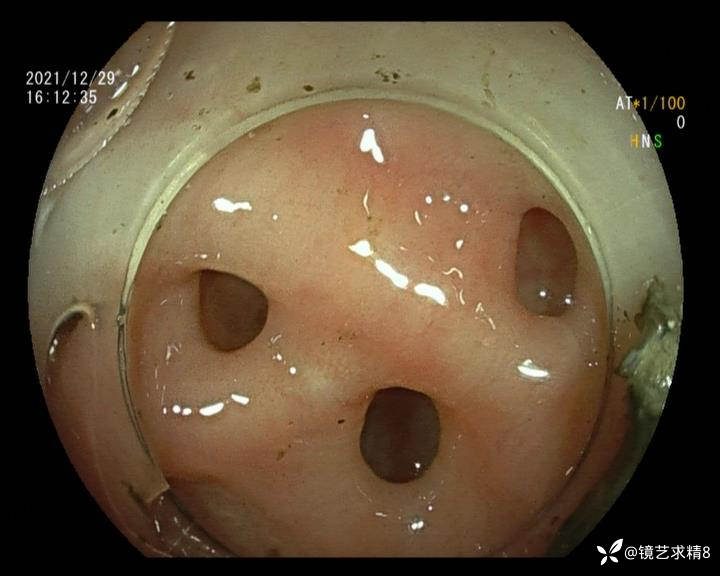

患者以消化道出血入院,胃镜未见异常,肠镜进入乙状结肠就看到很多憩室,同时还看到肠腔用清肠药后移动下来1枚尖锐的枣核,这么多憩室,这个枣核扎入憩室的机会非常大,推测应该是掉入一坑🕳就算出来还会有很多坑🕳🕳🕳等着,掉入憩室内很容易刺破血管,这可能就是消化道出血的原因,继续前进可以看到有一些憩室内翻,还有一些息肉,问题来了,那么多憩室,犯罪分子是抓住了,它在那些憩室内作过案?到达回盲部后挨个冲洗,但憩室大小又不足以把镜头进入憩室内观察,针对有血块的憩室冲洗后可疑出血的以夹子闭合或套扎,取出枣核,如果有锥形透明帽可能钻入憩室精准电凝效果更好,若内镜下操作失败介入治疗成功率更高,经内镜下治疗后观察未再出血出院。

亚洲人群结肠憩室主要发生在右半结肠,然后随着年龄的增长而延伸到左半结肠和双侧结肠。相比之下,欧美人群80%的结肠憩室好发于左半结肠,其中乙状结肠憩室占 70%,而大多是假性憩室。 然而,与憩室炎主要发生在左半结肠不同,东西方人群的憩室出血均主要发生在右半结肠,可能与右半结肠的憩室更宽大及憩室血管更易受到损伤相关。